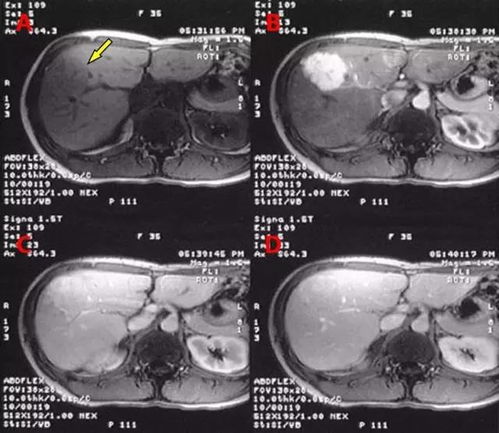

当我们发现肺部硬块时,如何判断其良恶性呢?可以从以下几个方面进行鉴别。通过影像学检查,如CT或MRI,可以观察肿块的形态、密度及与周围组织的关系。良性肿块通常边界光滑,而恶性肿块可能呈现分叶状、毛刺征或胸膜凹陷征。生长速度也是判断良恶性的一个指标,恶性肿瘤往往进展较快。要确诊肿块的性质,病理检查结果是金标准,可以通过穿刺活检或手术切除后进行病理分析。